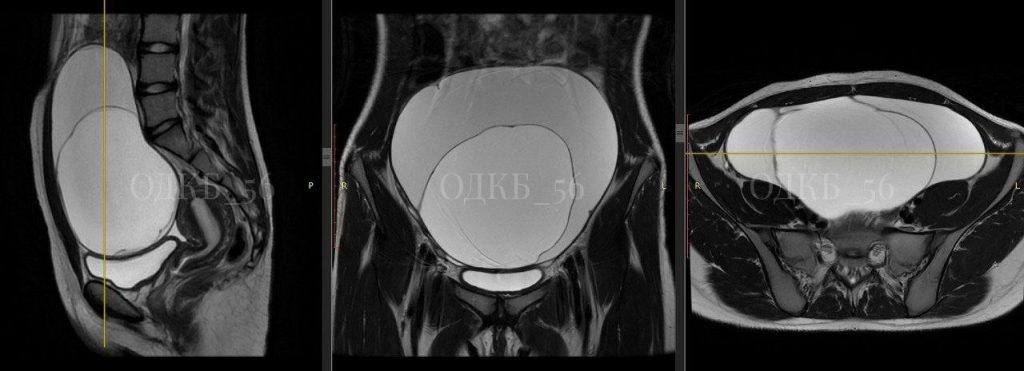

УЗИ и МРТ показало, что обнаружено объемное образование больших размеров. Было даже подозрение на злокачественную опухоль. Хирурги ОДКБ провели операцию.

— Образование, исходящее из правых придатков матки, размером 20 см в диаметре, было удалено в полном объеме, хотя было сложно, из-за выраженных спаечных процессов в малом тазу, — рассказали в ОДКБ.

Был поставлен диагноз — муцинозная цистаденома. Опухоль оказалось доброкачественной. Через неделю девочка была успешно выписана из больницы.